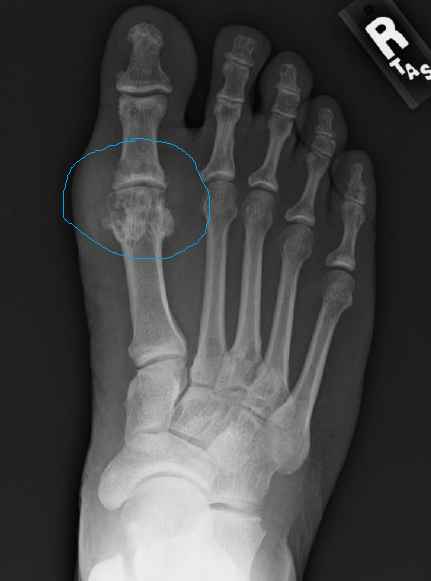

Identify

Jones fracture

(fracture of the base of the 5th metatarsal)

tophi (gout)